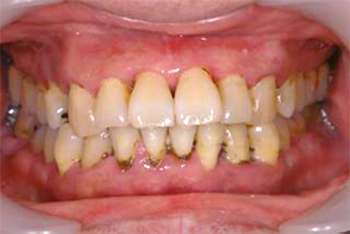

向かって右奥歯の根が露出してしまっています。

噛み合わせや不適切な治療や歯ブラシの仕方によって、歯周病が進行しきった状態です。

こうなってしまうと残念ながら救う手だてはありません。

前方の歯の詰め物、被せ物も決して精度高い治療とは言えません。歯周病は早期発見・早期治療が大切なのです。